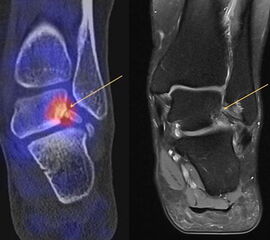

Abbildung 2.3.

Klärung bei Schmerzen im rechten OSG bei OCL an der medialen Talusschulter. Z. n. OSG-Distorsion vor 2 Jahren und Z. n. OSG-Fraktur / Syndesomosenruptur. Ausgedehnte OCL, hier jedoch kein erhöhter Knochenmetabolismus; lediglich Nachweis einer Stressreaktion im Bereich der Synchondrose eines Os trigonum als Schmerzursache.

Zum Lesen der Bildbeschreibung und zur Vollansicht bitte das Bild anklicken. Bild: H. C. Rischke

Bei der Differenzialdiagnose von Impingement-Syndromen am Sprunggelenk kann das SPECT/CT den Ort der Symptome- verursachenden Stressreaktion darstellen 32. Eine typische Ursache für ein posteriores Impingement kann ein Os trigonum sein. Scherkräfte im Bereich der Synchondrose eines Os trigonum lösen hypermetabole Stressreaktionen aus. Die Exzision des Os trigonum stellt eine erfolgreiche Therapie dar, sodass der Befund eines szintigraphisch aktivierten Os trigonum den Erfolg einer chirurgischen Therapie vorhersagen kann 3334.

In Abbildung 3.4. ist ein typisches Beispiel für ein symptomatisches Os trigonum dargestellt.